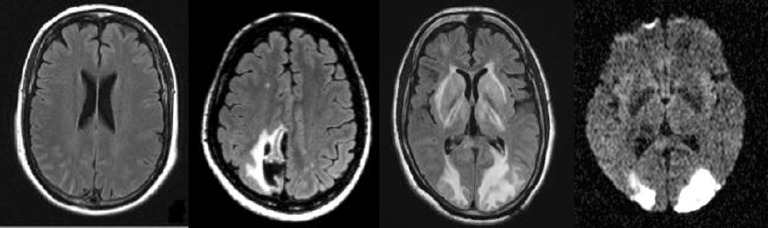

團隊發現RCVS患者的腦血管攝影中,可以看見血管一節節收縮的痕跡,收縮的狀況由小血管慢慢移到中央血管區,因此剛開始檢查時很難看見。RCVS會引起嚴重的併發症,例如可逆性腦後方白質病變或腦水腫達9-38%、缺血性腦梗塞達4-54%,以及腦出血可能高達20%,必須及早診斷。

文章插圖

左側是腦部血管收縮的圖,白色箭頭是血管收縮處,黑色箭頭指的是收縮後面有時伴隨血管擴張,因此血管看起來像念珠狀一節一節,右側則是恢復成正常的樣子。(圖/陳世彬提供)

榮陽頭痛研究團隊是全台第一個釐清RCVS臨床表現、建立檢查與治療標準流程、找出併發症的團隊,並開發新影像技術協助診治和探討病生理機轉,在RCVS領域中的研究成果可說是世界第一。